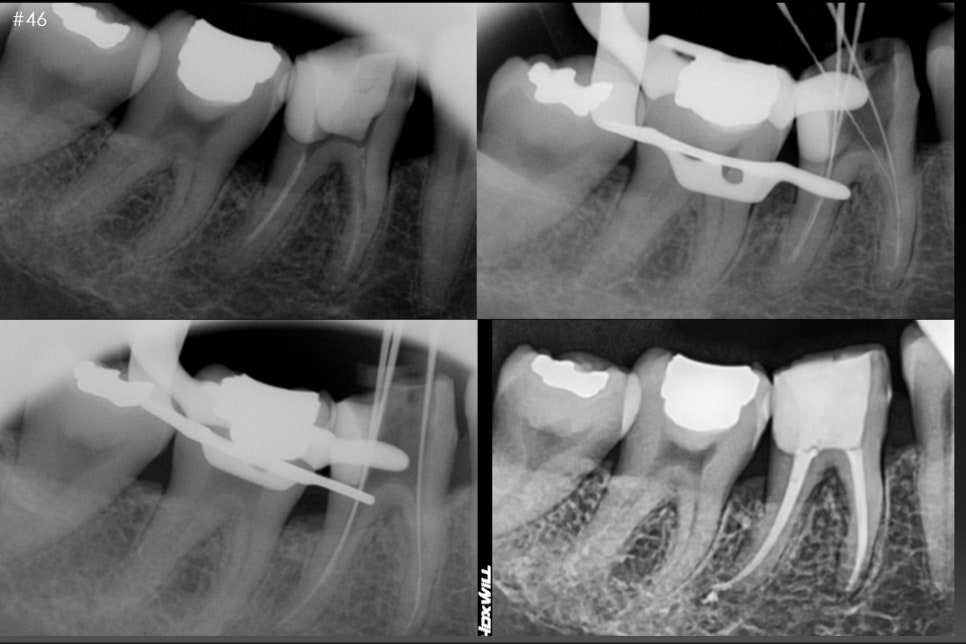

또 다른 증례입니다.

과거에 신경치료를 받았지만

치아 상부쪽 2차충치로 인한 내부 오염이 진행되고

뿌리안쪽까지 염증이 퍼져

재신경치료를 진행했습니다.

좌측상단사진이 초진사진입니다.

신경관안쪽의 재료들을 걷어내고 수 회 소독한 후

증상완화 확인후

우측아래 사진과 같이 뿌리끝까지 깨끗한 재료로 다시 밀봉한 후

통상적으로 보철 치료를 진행했습니다.

인접치아도 오래된 수복물로 내부오염이 되어있어

충치 제거 후 보철치료 완료하였습니다.^^

치료 시작 : 2023.11.23

치료 종료 : 2023.12.20